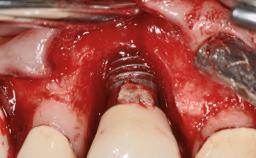

Oral implants are highly successful and offer long-term benefits, especially in the rehabilitation of edentulous patients or patients with oral defects following ablative tumor surgery (Albrektsson and coworkers 1986), and also after radiation therapy (Schiegnitz and coworkers 2014). With the number of implants placed globally going into the millions, implant dentists have observed some rare adverse events. Although carcinogenesis around implants is an exceedingly rare phenomenon, we recently reported about 15 patients treated for carcinomas adjacent to implants at our clinical department over a period of fifteen years (Moergel and coworkers 2014). The following case represents a patient of this cohort; it discusses possible risk factors and makes suggestions for a recall schedule. A 70-year-old woman was referred to our outpatient department for evaluation of a rapidly growing macroscopic alteration of the mucosa in the left mandible.

# of Implants 4

Type of Implants One-Piece